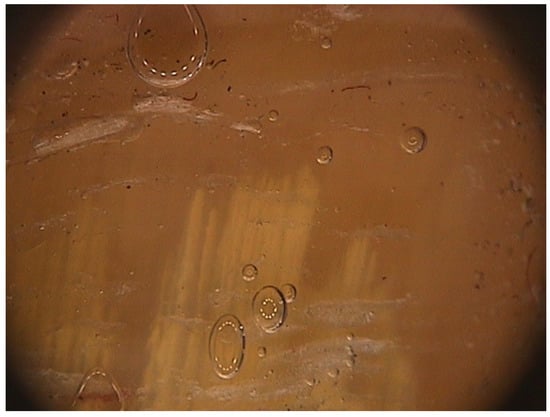

Digital dermoscopy, also called onychoscopy, is an easy and quick procedure that allows differential diagnosis of onychomycosis from the common nail dystrophies.

The peculiar features of DLSO, not seen on traumatic onycholysis and nail psoriasis, are [15]: (1) proximal margin of the onycholytic area showing jagged edge, with sharp structures, directed to the proximal fold (Figure 10); (2) longitudinal striae of different colors in the onycholytic nail plate; and (3) the overall appearance of the color of the affected nail plate in a matted variable discoloration resembling the aurora borealis.

Figure 10. Onychoscopy of DLSO, showing the typical proximal fringed (ragged) margin.